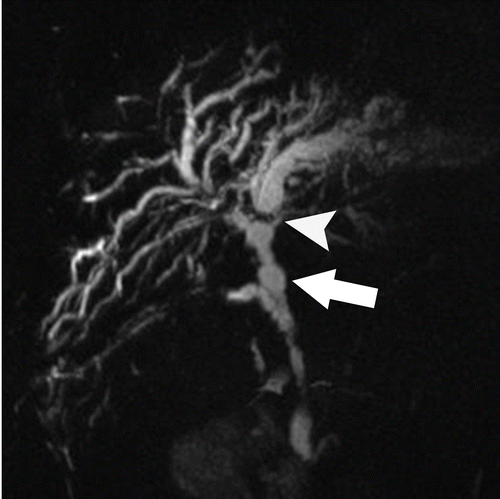

lung adenocarcinoma